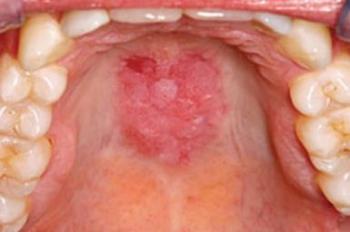

Klinikai kép. Az akut erythemás candidiasis hasonlít a soor gyepre, de nem fedi pszeudomembrán. Az érintett nyálkahártyaterület vöröses és fájdalmas. Az orális candidiasisnak ennél a formájánál valóban jelentős lehet a fájdalom, sőt a betegnek az általános közérzete is rossz. Ilyenkor a hifák felületesen behatolnak az atrophiás hámba. Ez a Candida forma (Candida dubliniensis) gyakori immunhiányos betegeken (AIDS), de más immundeficiens betegeken is előfordul (pl. hosszú távú antibiotikum-szedés vagy krónikus szteroidhasználat) (5.8. ábra).

5.8. ábra. Immundeficiens beteg candidiasisa